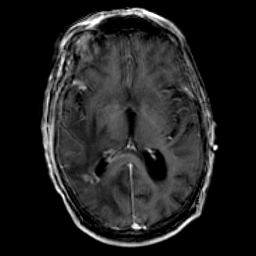

Glioma Overlay -- Slice #10

[Home][Help][Clinical] Slice 10